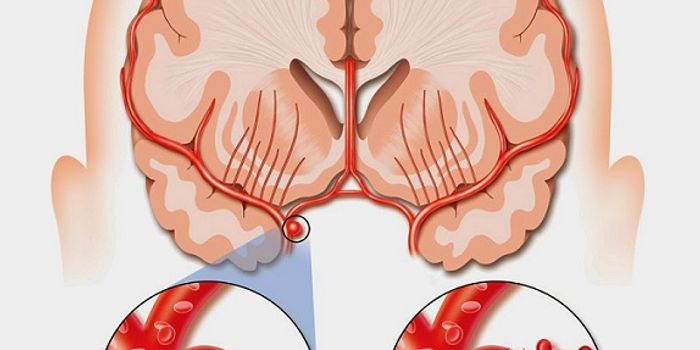

MAY 04, 2016NeuroscienceRupture of small blood vessels in the brain can cause hemorrhagic stroke and brain microbleeds, and finding the fastest ...

MAR 21, 2016NeuroscienceThe most common kind of stroke, an ischemic stroke, is caused by a blood clot which blocks the flow of oxygenated blood ...

MAR 17, 2016NeuroscienceBeauty parlor stroke syndrome? That can’t be a real thing right? Actually it is. There aren’t exact numbers ...

JAN 28, 2016NeuroscienceWhen a patient suffers a stroke, the key factor is time. Neurologists call it a Golden Window where “time is brain ...